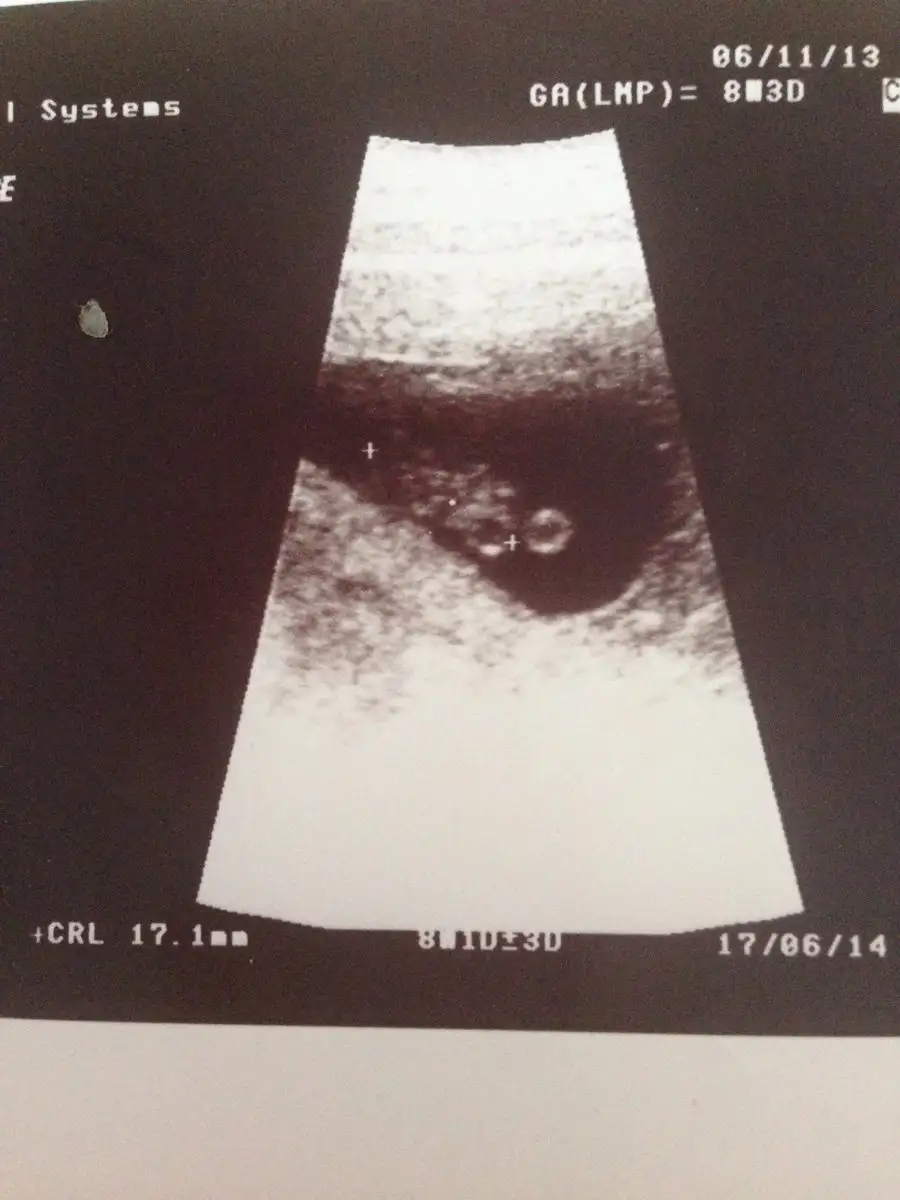

Oğlumun 8haftalık görüntüsüne baktım ama anlamadımRamzi teorisine göre ( bilimsel bir araştırma sonucuymuş ve %85 doğruluğu varmış). İlk 6-8 haftalık ultrason görüntüsüne göre bebeğin kesenin içersinde soldan ya da sağdan girişine göre cinsiyet tahmini yapılıyor. Bilimsel olunca tecrübeli annelerimiz yada anne adaylarımızdan yardım istiyoruz. Doğruluğu var mı öğrenmek adına :) Bizleri aydınlatırsanız çok seviniriz. bu teorieye göre;

Vajinal muayeneyle bakıldıysa eğer;

Sağdan girmiş gözüküyosa aslında solmuş ve ERKEK,

Soldan girmiş gözüküyosa aslında sağmış ve KIZ ,

Karından bakıldıysa eğer,

Soldan girmiş gözüküyosa gerçektede solmuş ve ERKEK,

Sağdan girmiş gözüküyosa gerçekte de sağmış ve KIZ,

Karından mı yapıldı canım?Eki Görüntüle 2236049

Ay kız galiba :) benim kızın görüntüsüne çok benziyor. Yuvarlak kese1 tabe 4 yasinda oglum haydu bilen desin kiz geliyormu :))

Bına göre soldan girmiş ve erkek çıkıyor, oğlunuz vardı değil mi ?Evet canım

Evet canım oğlum aslında orda 7haftalık ama ultrasonda önde gidiyorduBına göre soldan girmiş ve erkek çıkıyor, oğlunuz vardı değil mi ?